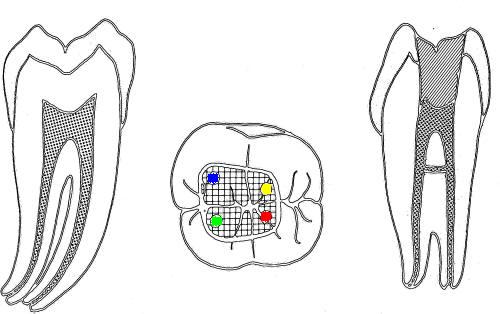

• En azul conducto mesio-vetibular

• En verde conducto mesio-lingual

• En rojo conducto distal

• En amarillo un cuarto conducto,  si el conducto distal se encuentra desplazado hacia lingual, existe una alta posibilidad de encontrar un cuarto conducto

Tres conductos en piso de cámara pulpar, el conducto distal se encuentra ensanchado en sentido buco-lingual, debe sospechar la existencia de dos conductos que comparten el orificio de entrada. Cámara intraoral X10 aumentos.